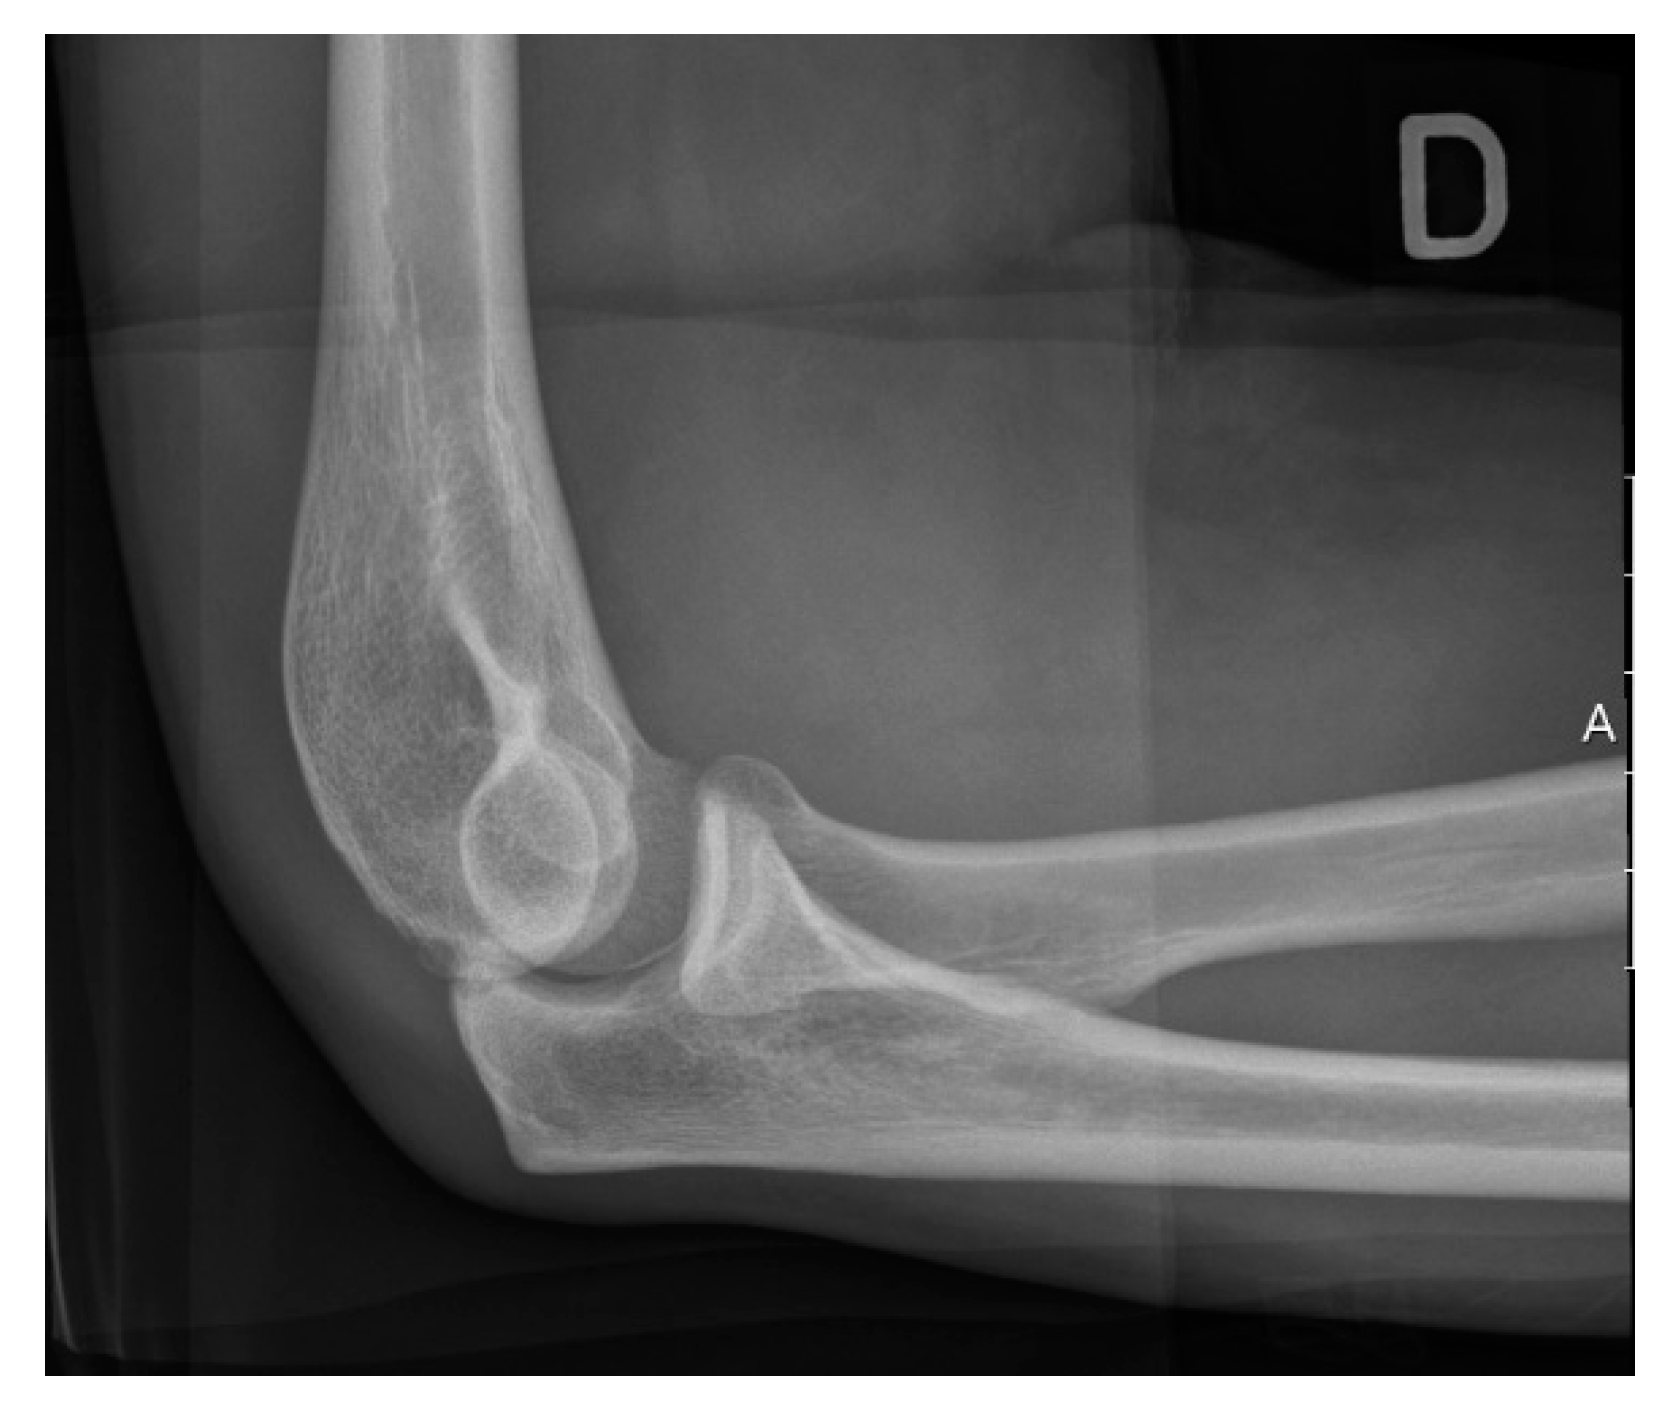

Figure 2.

Lateral radiograph of the elbow in a healthy patient.